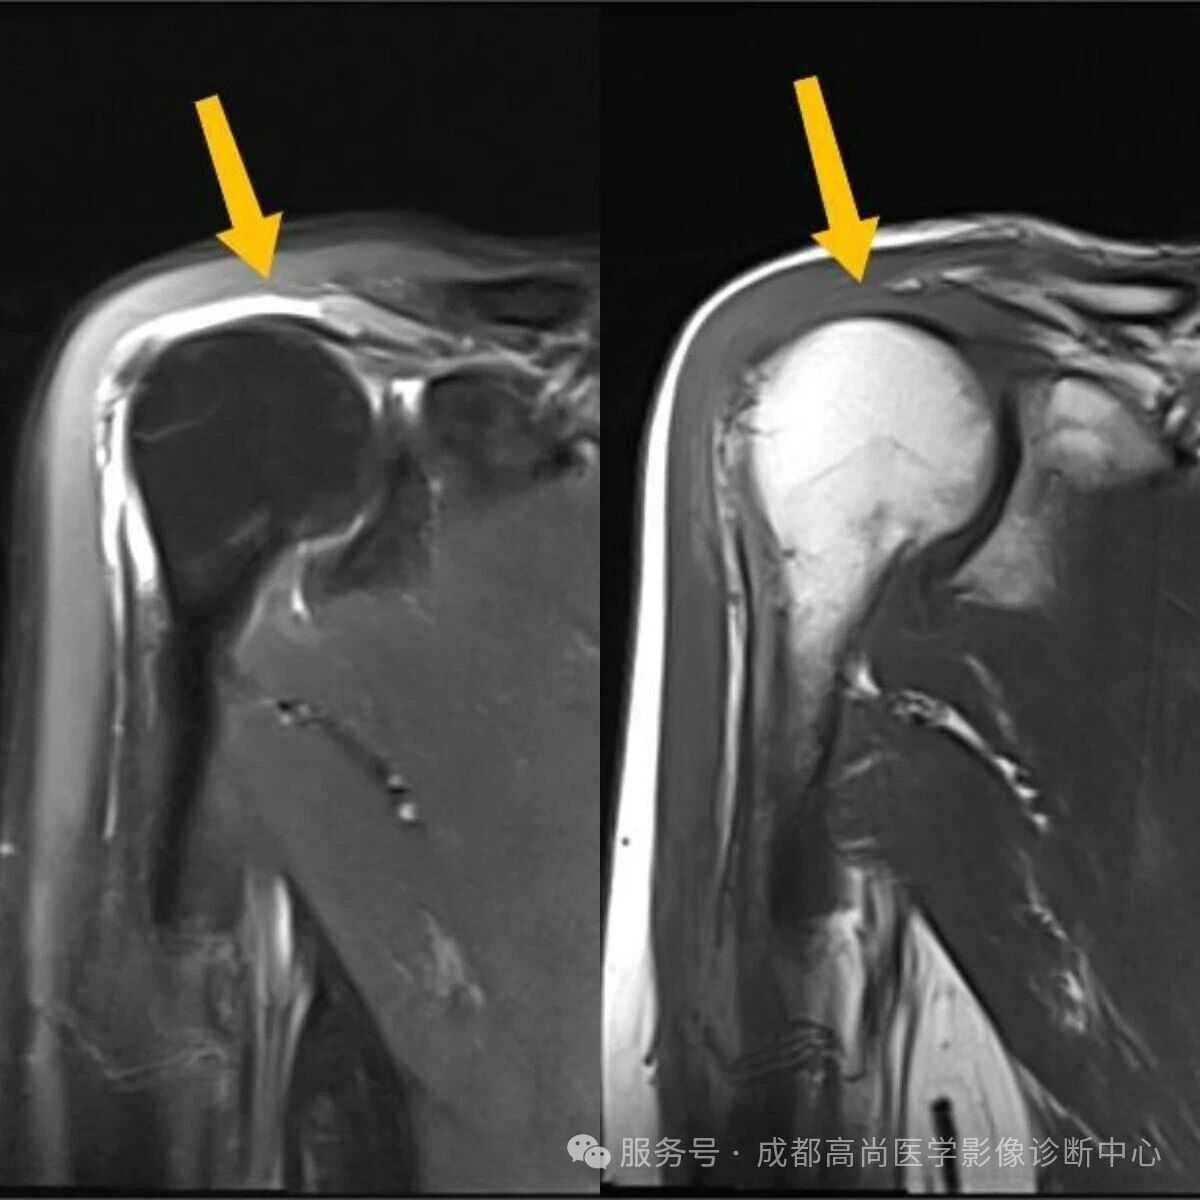

右肩 MRI 检查图像

图 1—5 MRI 平扫示右肩冈上肌肌腱失去正常形态结构,局部显示欠连续,肌腱附着点未见正常结构显示,提示冈上肌腱断裂。